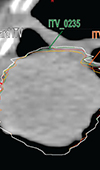

Dosimetric Implications of Number of Breathing Phases Used in the Definition of Internal Target Volume [ITV] in the Treatment of Non-Small Cell Lung Cancers Using Stereotactic Body Radiation Therapy (SBRT)

Determination of intrafraction motion in stereotactic body radiation therapy (SBRT) of non-small-cell lung cancer (NSCLC) usually involves generating... Read more